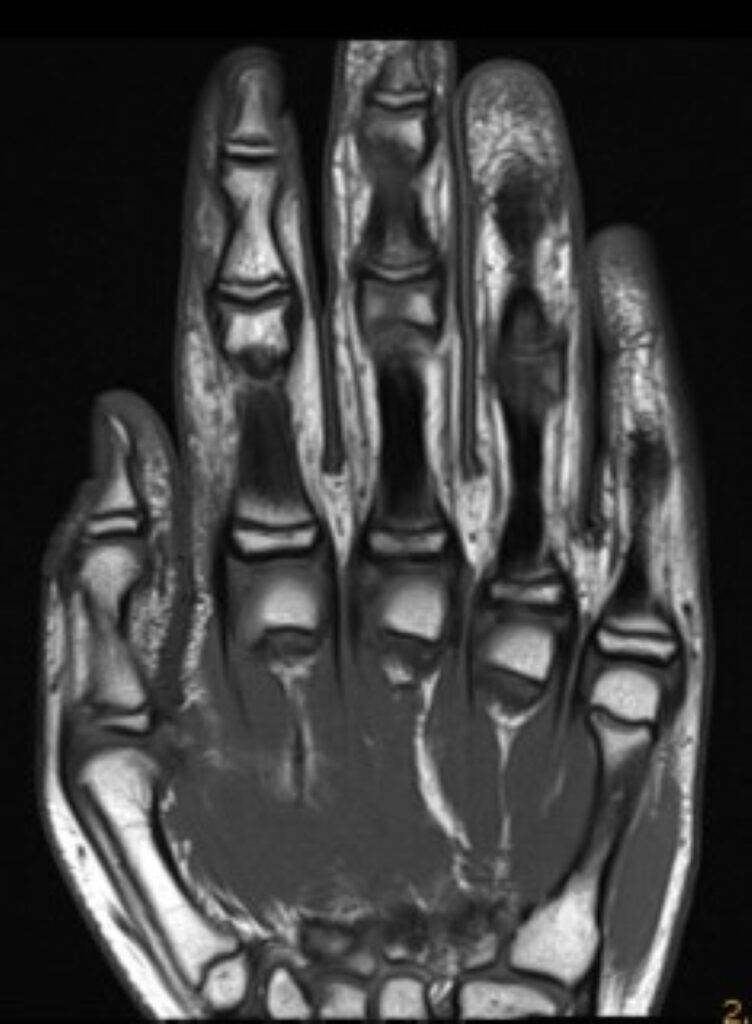

Je nach medizinischer Fragestellung wird eine spezifische Körperregion gescannt. Der Körper kann eingeteilt werden in Kopf und Hals, Thorax (Brust, Lunge, Herz), Abdomen und Becken (Bauchraum, Leber, Niere, Blase u.w.), Rücken (Wirbelsäule) und Extremitäten (Arme, Schulter, Beine, Füße).

Muskeln und GelenkeViele große Gelenke im Körper sind vielfältig, da diese aus Sehnen, Bändern, Gelenken und Muskeln bestehen. Diese lassen sich durch die MRT besonders gut betrachten, wie z.B. das Kniegelenk.

KnochenUnser Körper hat über 200 Knochen. In bestimmten Fällen ist eine MRT-Untersuchung zusätzlich zu einer Röntgenuntersuchung notwendig.

2. Verletzungen: oft kommt es zu Schulunfällen, dabei kann es zu Verletzungen in allen Körperbereichen kommen, je nach Verletzung kann zur genauen Diagnose eine MRT bei Kindern oder Jugendlichen notwendig sein

3. Erkrankungen des Bewegungsapparats: klagt Ihr Kind über Gelenk- oder Rückenschmerzen, Muskelschwäche oder ähnlichen Beschwerden, kann die MRT-Untersuchung helfen, die entsprechende Ursache zu finden